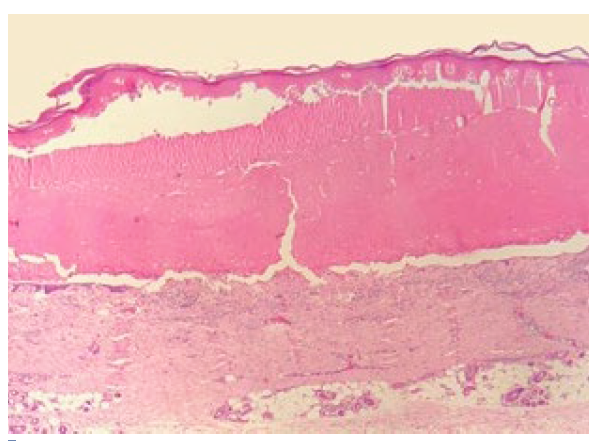

O exame histopatológico demonstrou bolha subepidérmica parcialmente reepitelizada e infiltrado inflamatório eosinofílico, sugerindo lesão antiga de penfigoide bolhoso (Fig.s 2 e 3).

Figura 3 Detalhe do assoalho da bolha: reepitelizacão e infiltrado inflamatório associado rico em eosinófilos (H&E, x10).